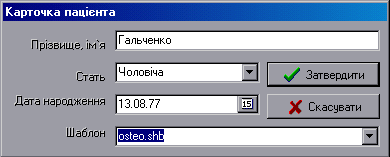

Програма роботи з базою даних представляє функції для створення картки пацієнта, пошуку, збереження ПГ й огляду інформації в базі.

База даних представляє собою список файлів. Використання довгих імен файлів в ОС Windows дозволяє називати файли прізвищами пацієнтів, що створює одразу зручну и гнучку систему збереження даних.

Реєстрація пацієнта:

Після цих дій на екрані з^явиться діалогове вікно зображене на рисунку 8.1.

Рисунок 8.1 – Вибір опції НОВИЙ ФАЙЛ

Кожний пункт реєстраційної карти при встановленому на ньому маркері виділяється [32].

Заповніть пункт "Прізвище, ім‘я", виберіть мишкою або за допомогою клавіатури стать, дату народження шаблон.

Поле шаблона вміщує список доступних шаблонів структур. Так в даній версії програми є такі версії як osteo.shb (вміщує структуру аналогічну структурі хребта) й dant.shb (стоматологія).